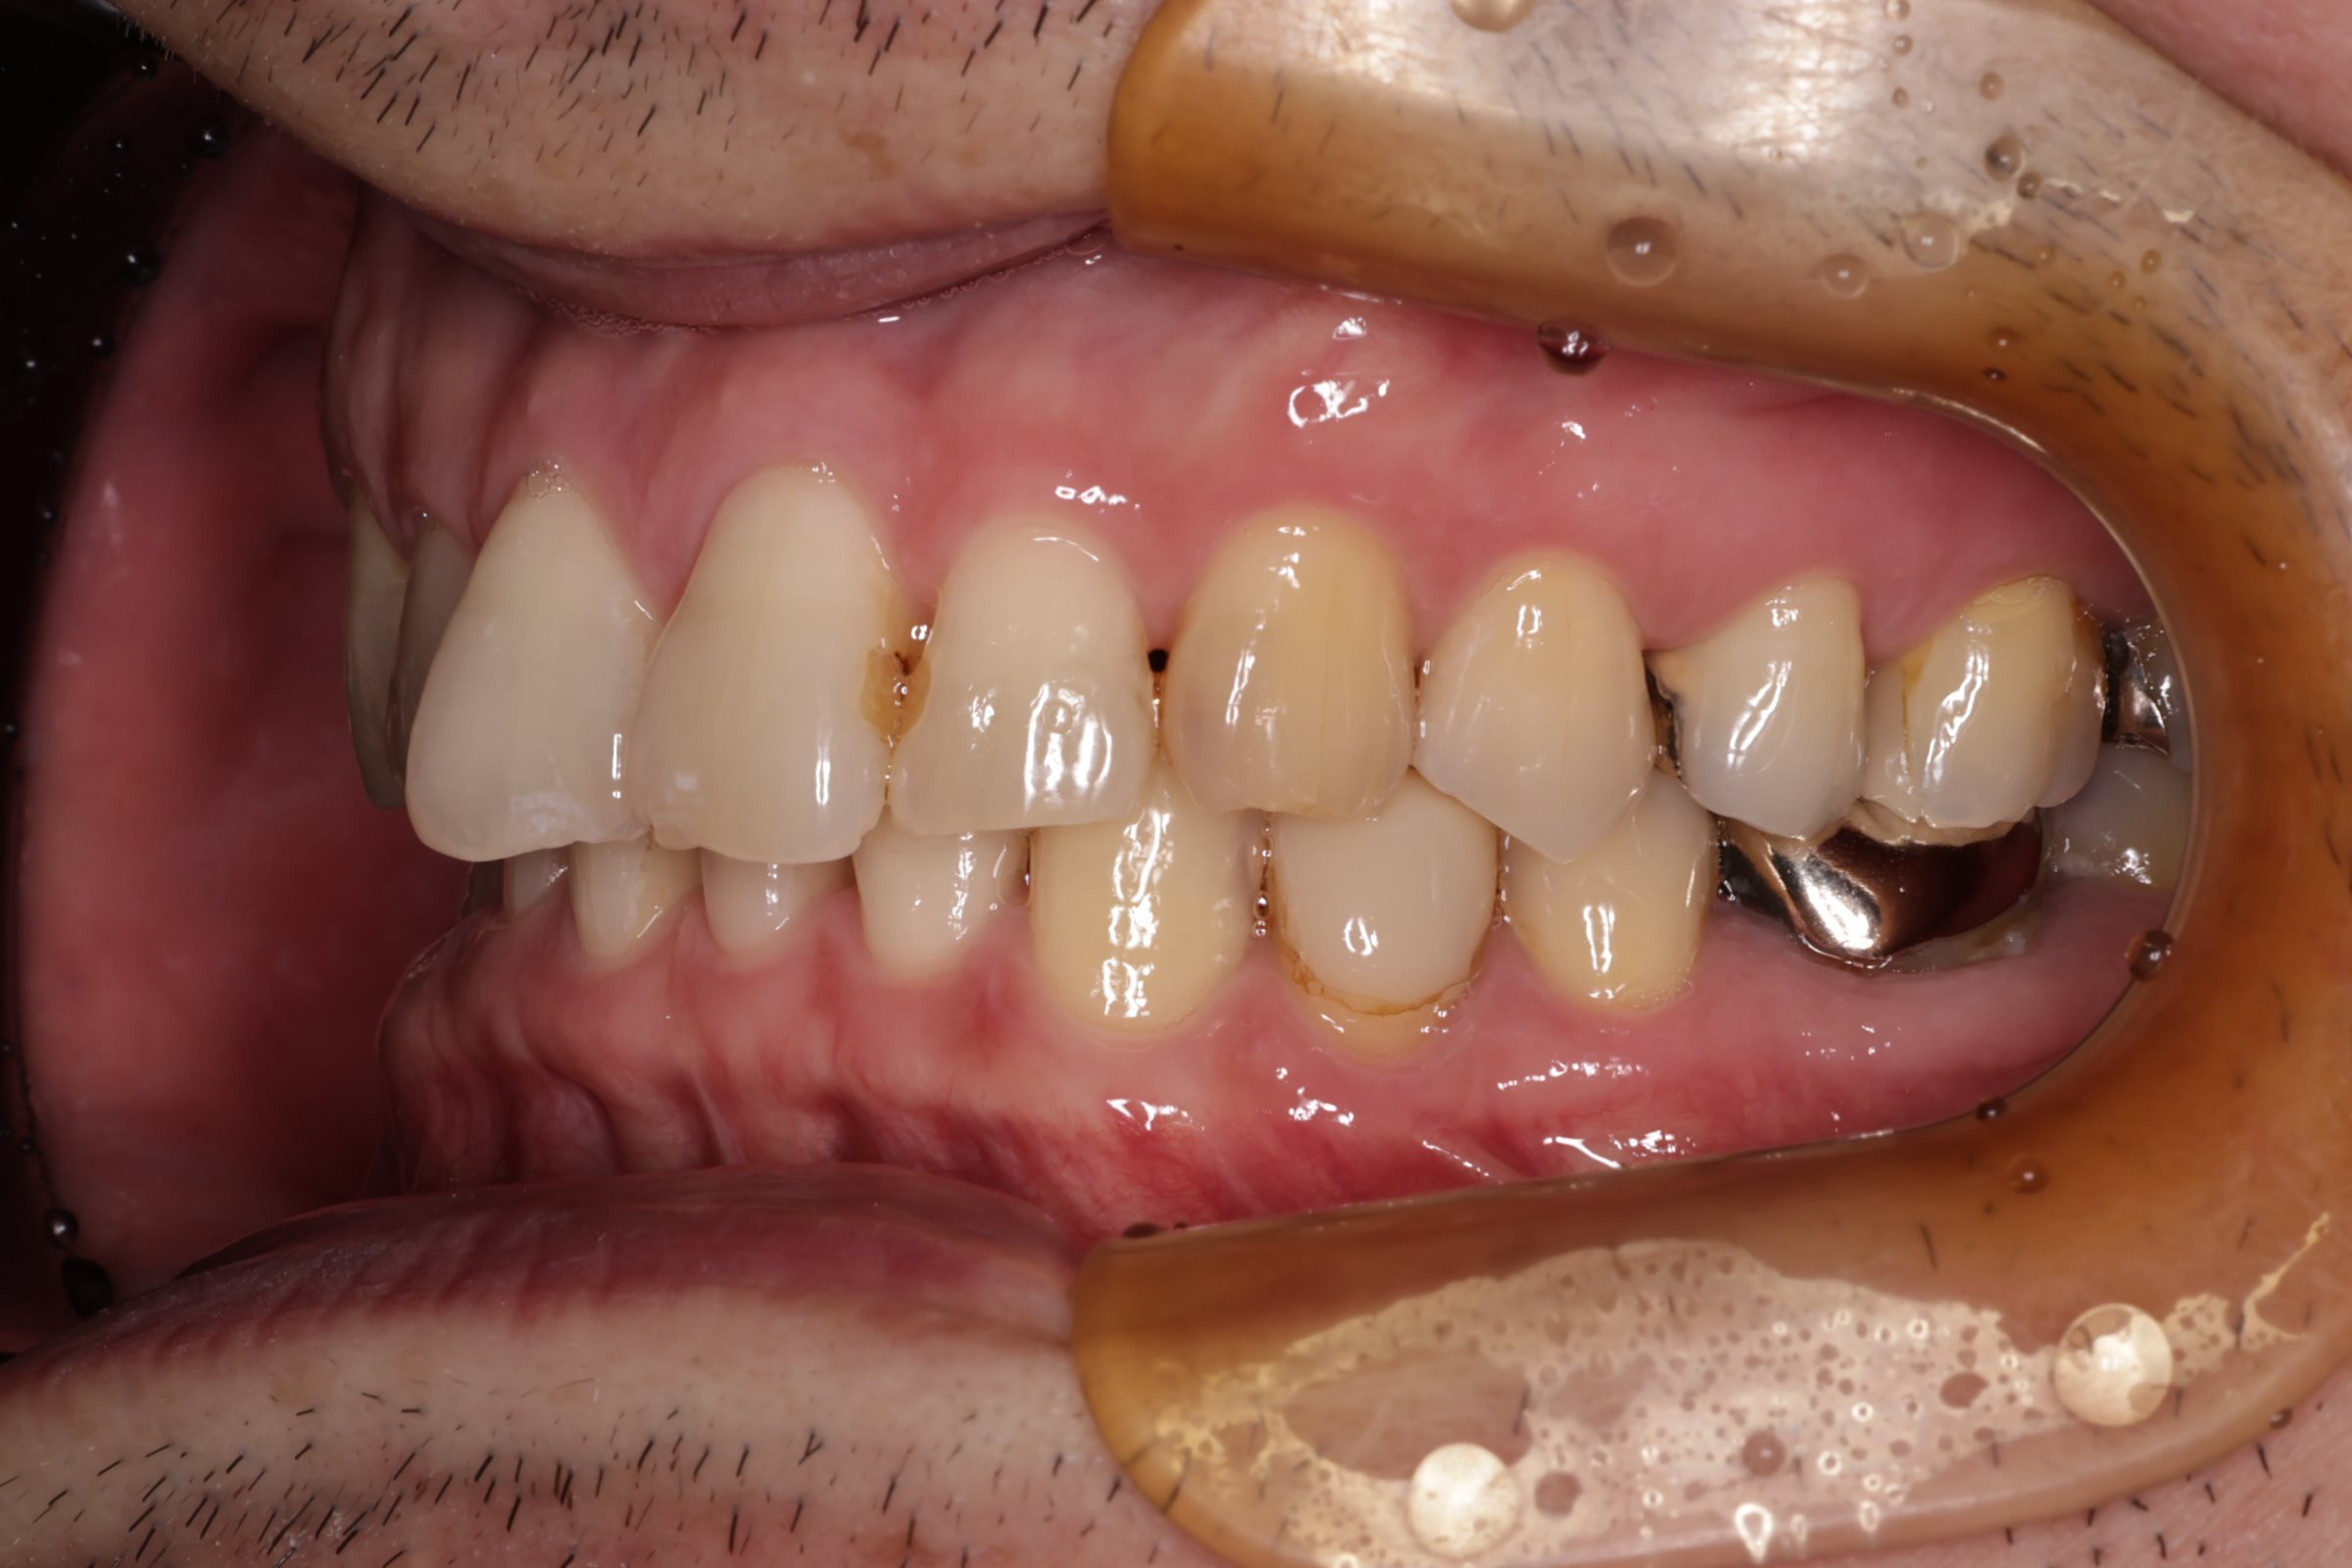

初診時の口腔内の状態:

口腔内には多数の銀歯(銀合金)が確認されました。患者様は過去に多くの虫歯治療を受けており、そのほとんどが保険適用内の銀合金で修復されていました。

患者様はパッチテストによりニッケルなどに対するアレルギーを持っていることが確認されており、口腔内の銀合金もアレルギーの原因となっている可能性が高いと診断しました。また、レントゲン画像を確認すると、被せ物や詰め物の内部、あるいは隙間から、虫歯(カリエス)や根の細菌感染が疑われる状態も確認されました。

Before